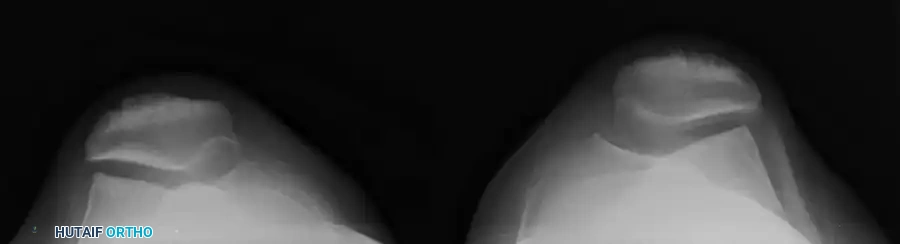

RADIOGRAPHIC EVALUATION OF THE PATELLOFEMORAL JOINT

A comprehensive radiographic evaluation is mandatory to assess the underlying osseous architecture, identify predisposing dysplastic factors, and rule out osteochondral shear fractures. Standard anteroposterior (AP) and lateral radiographs are routine, but specialized views are required to truly appreciate patellofemoral tracking and congruence.

Assessing Patellar Tilt and Sulcus Morphology

Once the appropriate views are obtained, the surgeon must analyze the images for signs of malalignment, tilt, and dysplasia.

Lateral Patellar Tilt:

On an axial or skyline view, the patella should sit symmetrically within the trochlea. A lateral tilt indicates tightness of the lateral retinaculum and potential insufficiency of the medial restraints.

Associated Surgical & Radiographic Imaging